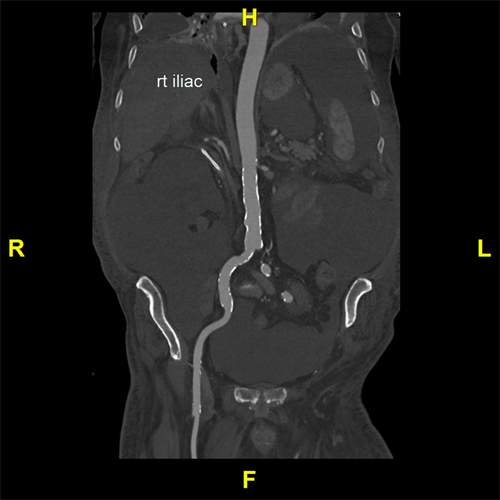

To create vascular distance measurements, the Stanford 3DQ Lab imports the imaging series into specialized software. A Curved Planar Reformation (CPR) is commonly created to view the vessel in question in a stretched-out manner without twists and turns (See Figure A). Two points are selected along the vessel, with the distance between them becoming a measurement of length. Determining where to create these measurements is dictated by a standardized process depending on the patient’s treatment needs or diagnosis.

Figure A: An example of a Curved Planar Reformation (CPR).